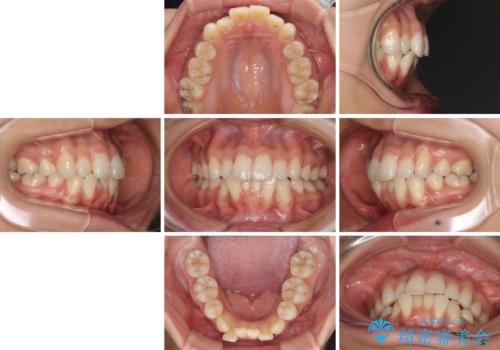

- 以前の矯正治療の後戻りにより、上下の前歯がでこぼこになってしまったことを気にして来院された患者様です。

口元がこれ以上突出することなく前歯の叢生が改善できるよう、歯と歯の間を削ってスペースを獲得し、インビザラインを用いて整えていくこととしました。